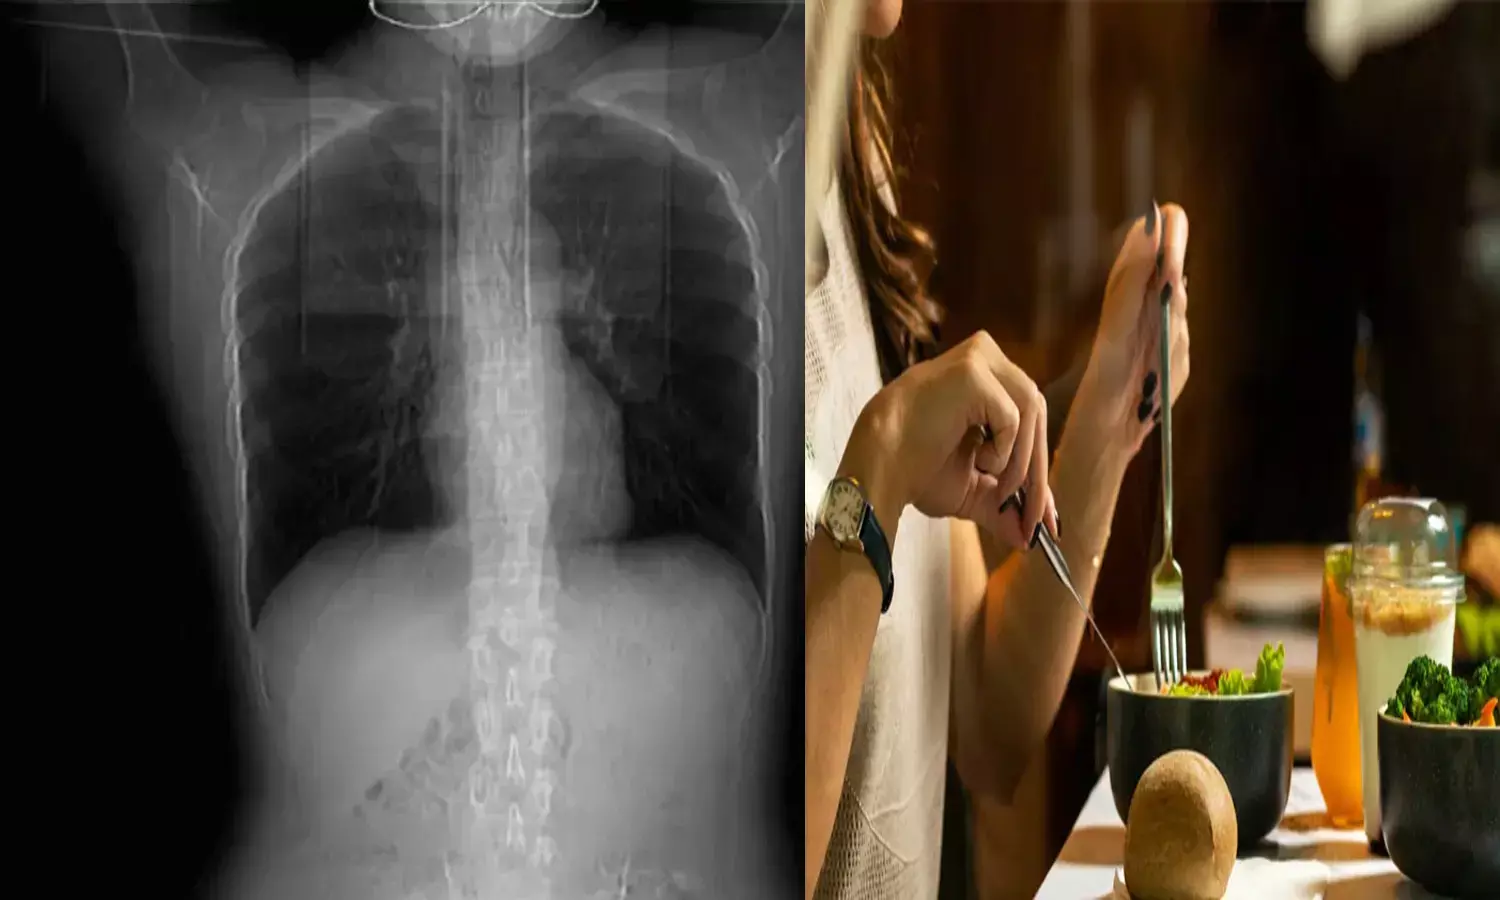

సాధారణంగా ఎవరికైనా అధికంగా దగ్గు వస్తే.. గొంతులో మంట, ఒక్కోసారి కడుపులో నొప్పి, గొంతు నొప్పి, మాటలో తేడా రావడం సహజం. కానీ.. ఓ మహిళ దగ్గితేనే పక్కటెముకలు విరిగిపోయాయి. ఇదెక్కడి చోద్యం అనుకుంటున్నారా. ఇది నిజంగా జరిగింది. చైనాలోని షాంఘై నగరానికి చెందిన హువాంగ్ అనే మహిళ ఇటీవల ఘాటైన ఆహారం తీసుకుంది. దాంతో ఆమెను దగ్గు ఊపిరాడనివ్వకుండా చేసింది. దగ్గుతున్న సమయంలో ఛాతీలో నొప్పి వచ్చినా.. పట్టించకోలేదు.

ఆ తర్వాత నొప్పి పెరగడంతో.. వైద్యులను సంప్రదించింది. స్కానింగ్ చేసిన వైద్యులు ఛాతీలోని నాలుగు పక్కటెముకలు విరిగిపోయినట్టు గుర్తించి ఆశ్చర్యపోయారు. అందుకు వైద్యులు చెప్పిన కారణం ఏంటో తెలుసా ? బాధిత మహిళ ఉండాల్సిన దానికంటే చాలా తక్కువ బరువు ఉండటం. తక్కువ బరువు ఉండడం వల్ల శరీరంలో ఎముకలకు ఆధారంగా ఉండే కండరం ఎదగలేదని చెప్పారు. దీంతో ఆమె దగ్గినప్పుడు అవి విరిగిపోయాయని చెప్పారు. ప్రస్తుతం ఆమెకు చికిత్స అందిస్తున్నామని, కోలుకున్న తర్వాత వ్యాయాయం, సరైన భోజనం తీసుకోవడం ద్వారా కండరాన్ని పెంచుకోవచ్చని అన్నారు.